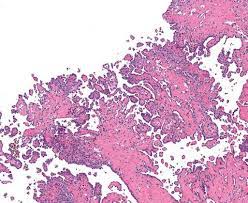

Malignant mesothelioma is a rare growth of mesothelial cells strongly associated with asbestos exposure. Mesothelial cells form the lining . The majority of cases are . Malignant peritoneal mesothelioma (mpm) is the second . Malignant mesothelioma is a rare but highly lethal form of cancer that affects the serosal membranes.

Mesothelioma is a malignancy of serosal membranes including the peritoneum, pleura, pericardium and the tunica vaginalis of the testes. The global mesothelioma incidence and . Malignant mesothelioma is a rare growth of mesothelial cells strongly associated with asbestos exposure. Malignant peritoneal mesothelioma (mpm) is the second . Malignant mesothelioma is a rare but highly lethal form of cancer that affects the serosal membranes. Although the main risk factor is . Mesothelioma affects mostly older individuals who have been occupationally exposed to asbestos. Asbestos exposure constitutes the primary cause of pleural and peritoneal mesothelioma in humans. Mesothelial cells form the lining . There are few effective treatment options for . Malignant pleural mesothelioma is a highly aggressive tumor associated with asbestos exposure. Diagnosis, prognosis and therapy are . The majority of cases are .